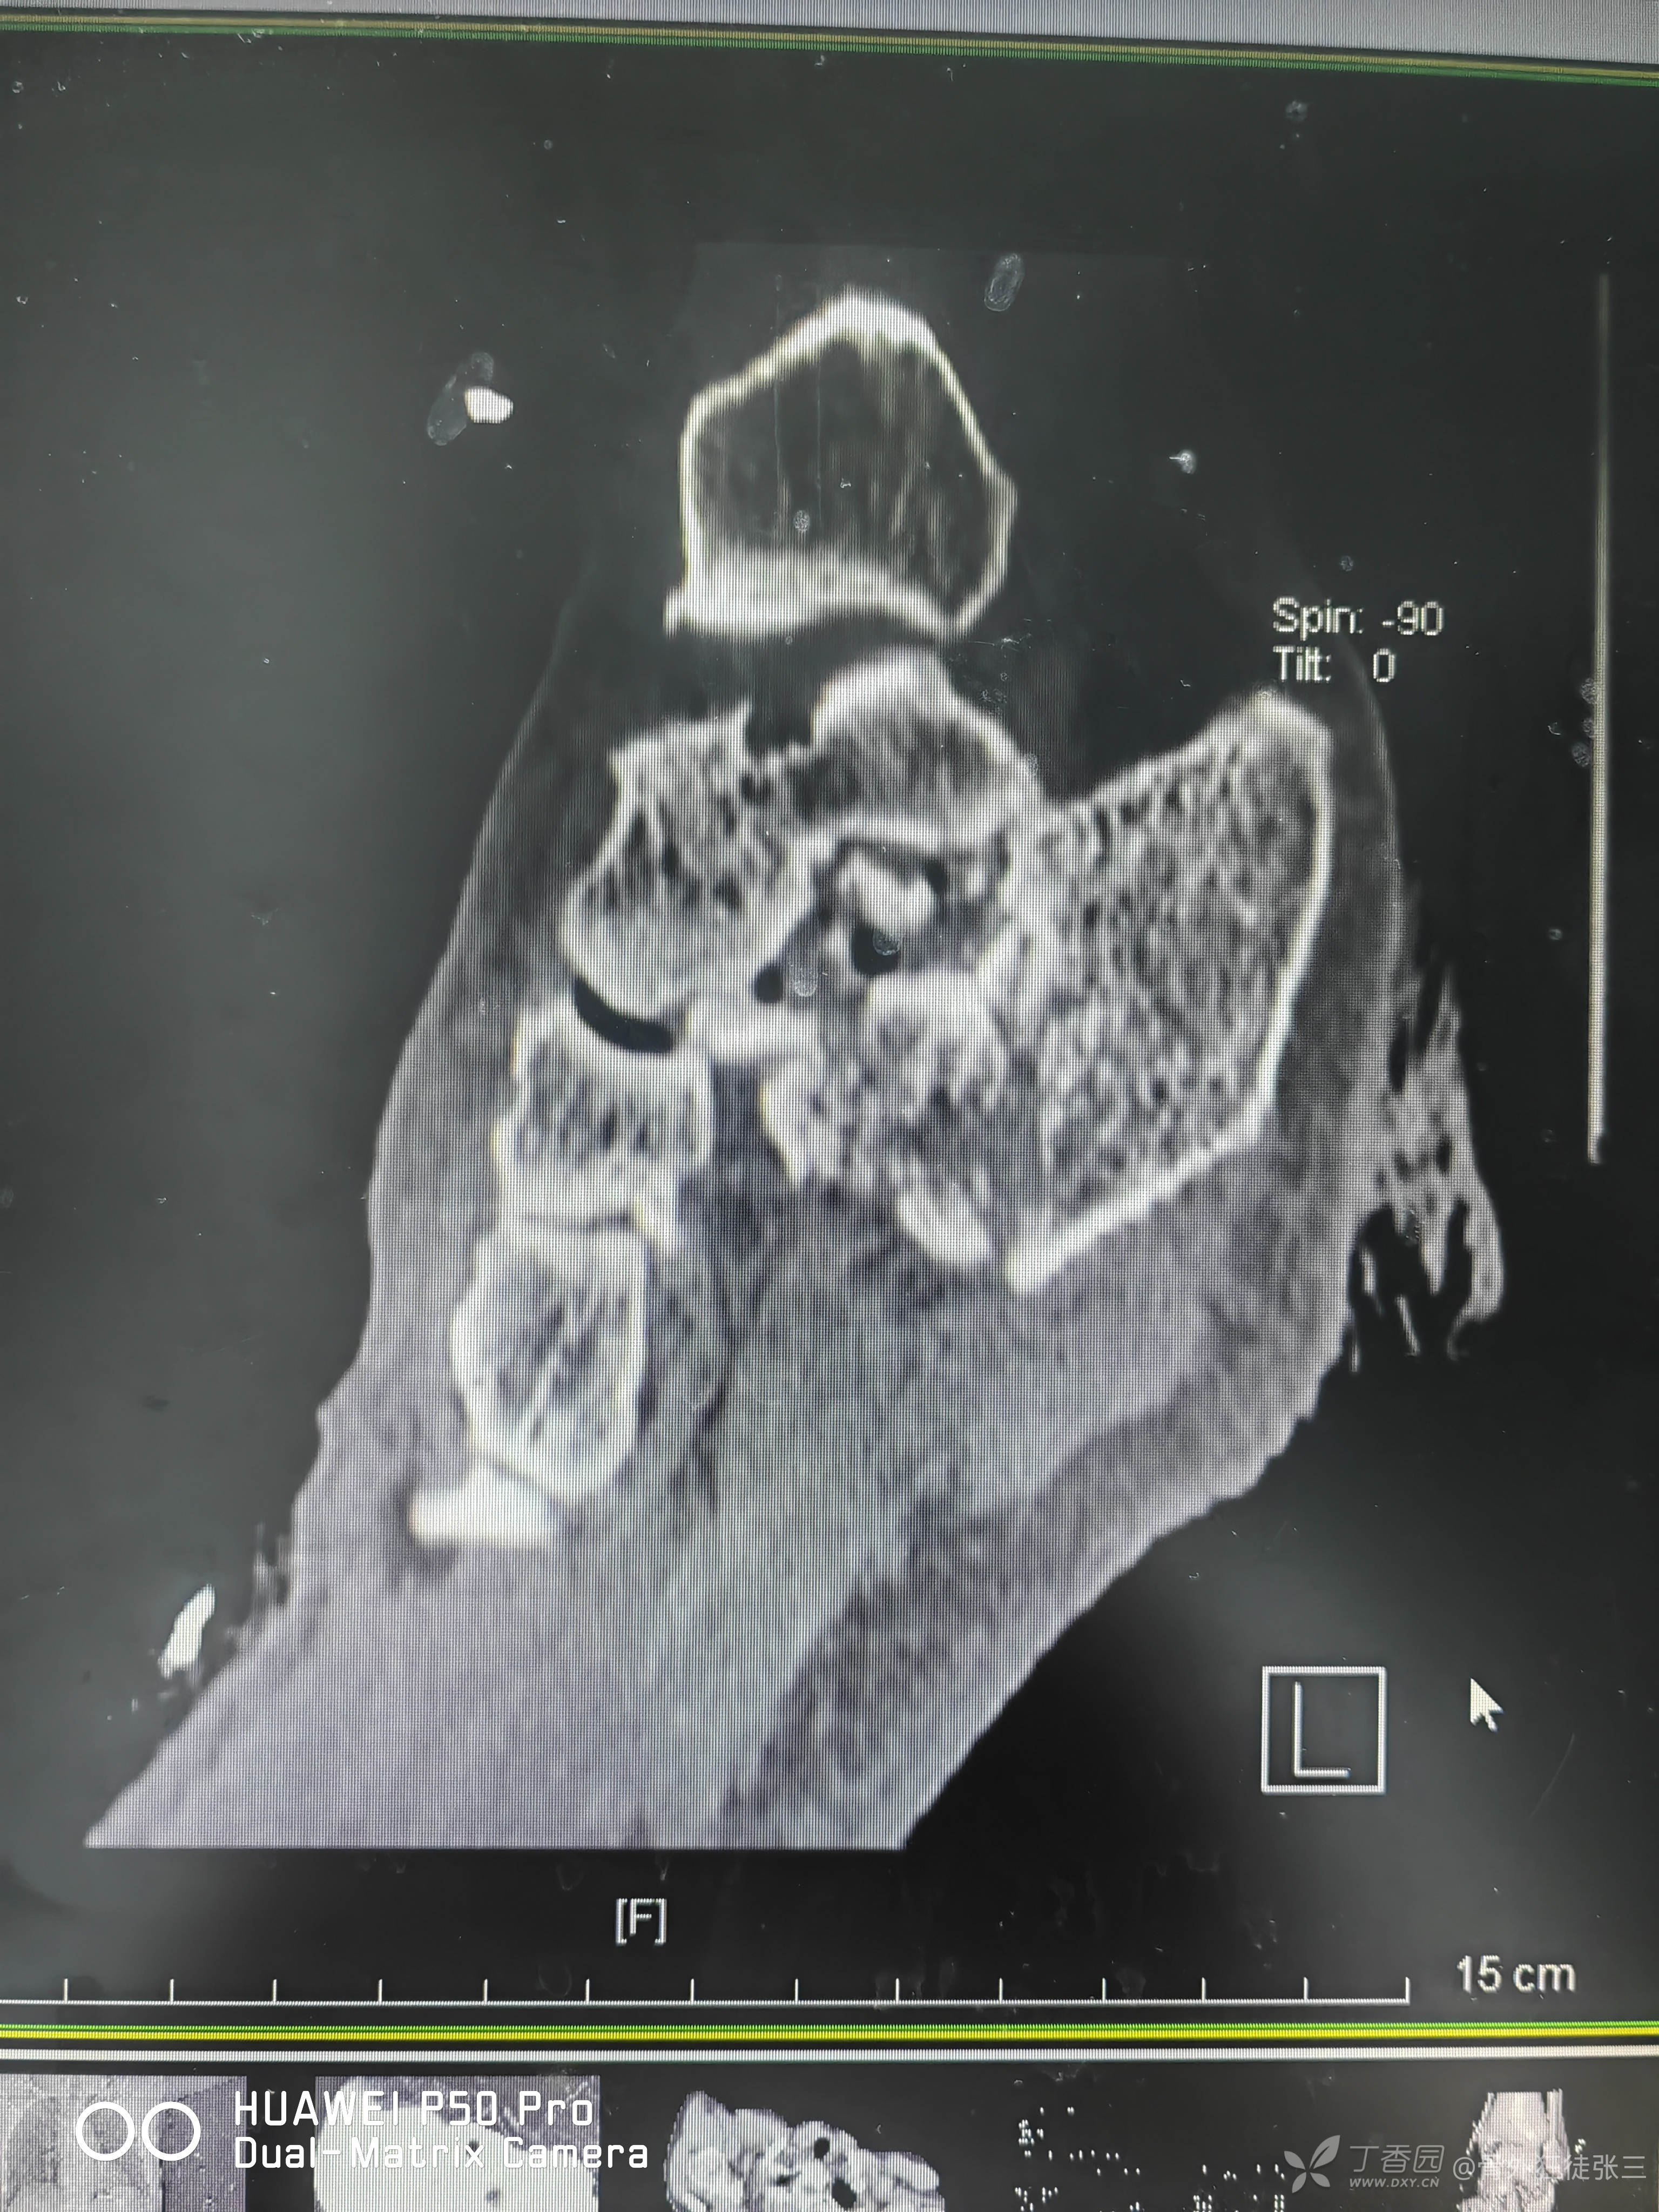

目前的影像学

第一跖骨骨缺损处为抗生素骨水泥